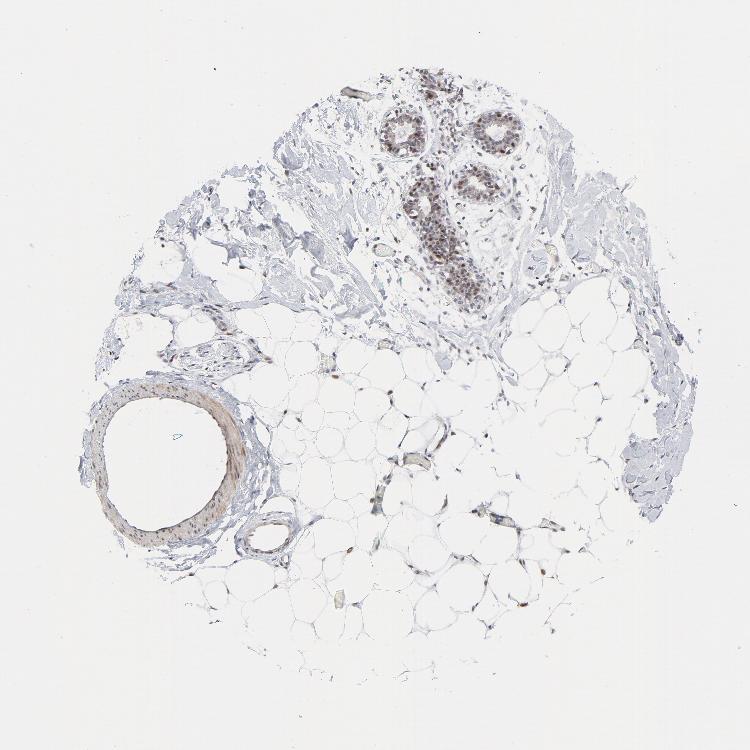

BREAST - Antibody stainingi

Antibody staining in the annotated cell types in the current human tissue is reported as not detected, low, medium, or high, based on conventional immunohistochemistry profiling in selected tissues. This score is based on the combination of the staining intensity and fraction of stained cells.

Each image is clickable and will lead to virtual microscopy that enables deeper exploration of all samples and also displays staining intensity scores, fraction scores and subcellular localization as well as patient and tissue information for each sample.

Antibody HPA052625Antibody CAB004300Antibody CAB004674

Adipocytes Not detectedMediumMedium

Glandular cells MediumMediumHigh

Myoepithelial cells MediumMediumHigh